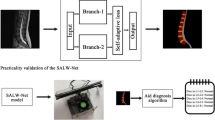

The objective of our team is to develop a multi-element identification system for the visual field of endoscopic spine surgery using deep learning algorithms and to evaluate the feasibility of this system.

We established an image database by collecting surgical videos of 48 patients diagnosed with lumbar disc herniation, which was labeled by two spinal surgeons. We selected 6000 images of the visual field of percutaneous endoscopic spine surgery (including various tissue structures and surgical instruments), divided into the training data, validation data, and test data according to 2:1:2. We developed convolutional neural network models based on instance segmentation—Solov2, CondInst, Mask R-CNN and Yolact, and set the four network model backbone as ResNet101 and ResNet50 respectively. Mean average precision (mAP) and frames per second (FPS) were used to measure the performance of each model for classification, localization and recognition in real time, and AP (average) is used to evaluate how easily an element is detected by neural networks based on computer deep learning.

Our team has developed a multi-element identification system for the visual field of percutaneous endoscopic spine surgery adapted to the interlaminar and foraminal approaches, which can identify and track anatomical tissue (nerve, ligamentum flavum, nucleus pulposus, etc.) and surgical instruments (endoscopic forceps, an high-speed diamond burr, etc.), which can be used in the future as a virtual educational tool or applied to the intraoperative real-time assistance system for spinal endoscopic operation.